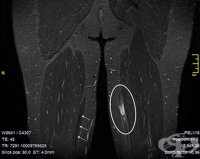

S76.3 Травма на мускулите и сухожилията от задната мускулна група на ниво бедро

Заболявания

Мускулите от задната мускулна група са: - M.semitendinosus; - M.semimembanosus; - M.biceps femoris. ...